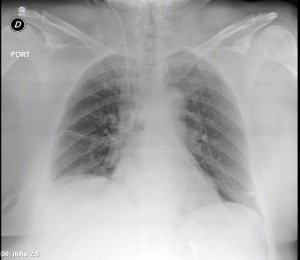

The current treatment algorithm, which often starts as several weeks of outpatient antibiotics, (usually initiated for treatment of community acquired pneumonia that develops into a parapneumonic effusion), that engenders an even longer period after subsequent follow up chest x-rays, then CT scan fail to show improvement.

A pneumonia in late September, becomes an effusion in October, then progresses to empyema as various strategies are attempted and fail.  One antibiotic is switched to another, a pigtail is placed in radiology (with partial results), then perhaps, a larger tube, and fibrinolytics.  Then, only then – is the thoracic surgery service consulted.